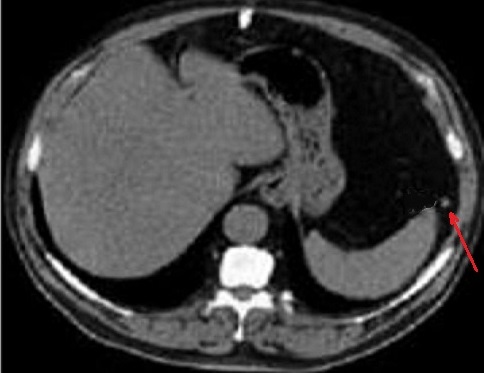

Aspect

radiologique une rate sur numeraire a inferieure de

la la rate principale ( fleche rouge ) .Ce coupe

frontale ( coronal) se prise au temps de precoce

apres injection de contrast intra veineuse . Sa

parenchyme est rehaussement hyperdensité heterogène

au temps de precoce . Image radiologique TDM plus C+

coupe coronal . |